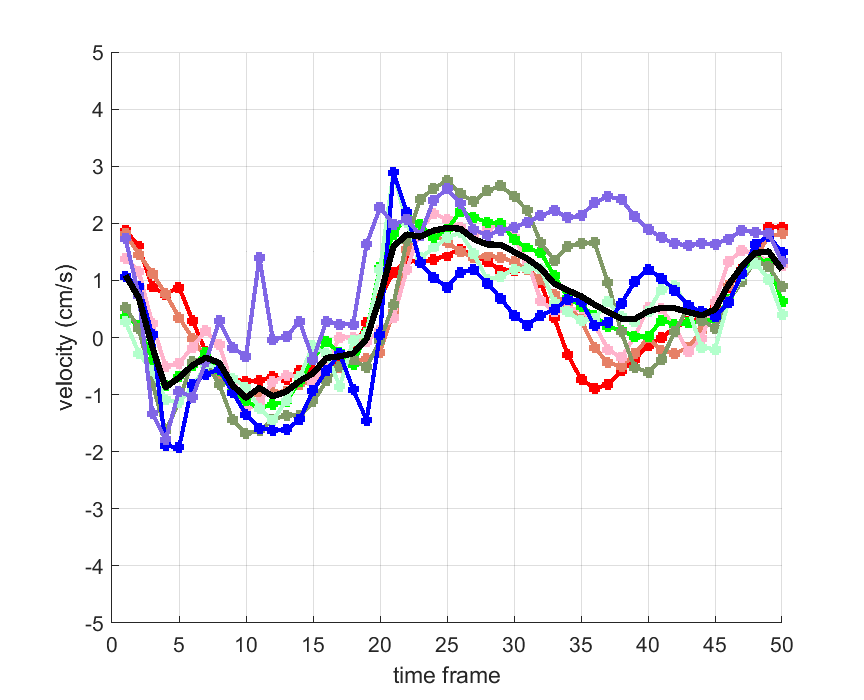

Time courses of the estimated translational component per subject, frame, slice and volume along the 3 velocity directions x, y and z are presented in Fig.6 - Fig.8.